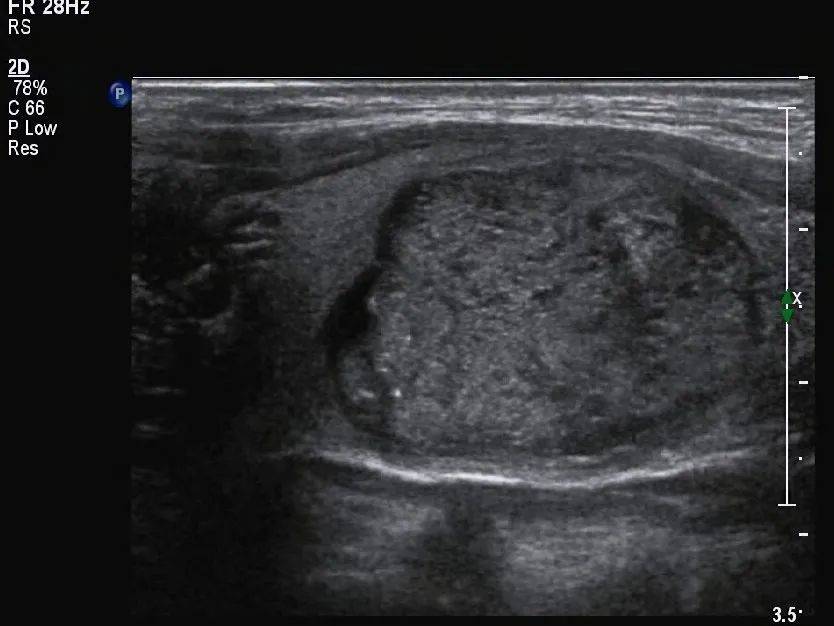

甲状腺形态失常,左侧叶增大,内部回声不均匀,见囊实混合性结节,大小约 33mm×19mm×28mm ,形态规则,边界清,纵横比 <1 ,内部以实性为主,实性部分见少许散在点状强回声(图 1 、图 2 ),结节周边伴低回声声晕,声晕厚度不均匀(图 3 ), CDFI:结节周边见环绕血流信号,内部见不规则分布的血流信号,局部较丰富(图 4 、图 5 )。SMI:结节局部微细血流信号丰富(图 6 )。

图 2 结节周边有环绕的低回声带,厚薄不均